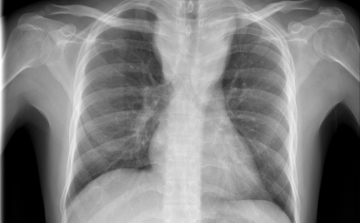

Magyarországon halnak meg a legtöbben tüdőrákban az EU-ban

Az Európai Unióban Magyarországon a legmagasabb, az összes halálok között 27 százaléknyi a tüdőrák okozta halálozások aránya - hangzott el az M1 aktuális csatorna csütörtöki műsorában.